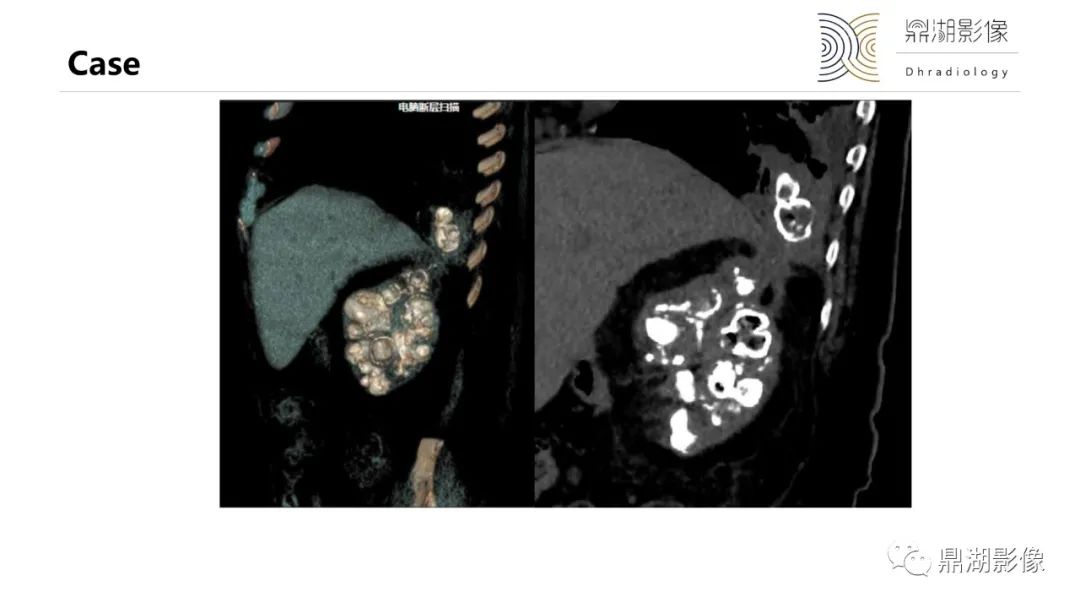

黄色肉芽肿性肾盂肾炎(Xanthogranulomatous pyelonephritis ,XGP)又称泡沫细胞肉芽肿,是一种少见的肾实质及肾周组织以肉芽肿组织改变为主的慢性非特异性炎性病变。

可见于所有年龄组,中老年患者多见,男、女比例1:2。

XGP的病因尚不明确, 与泌尿系感染、自身免疫机能低下及泌尿系结石、梗阻等因素有关,常见致病菌为大肠杆菌和变形杆菌。糖尿病患者的发病率有所增加。

主要临床表现不典型,全身症状表现为身体不适、体重减轻和低烧等,可有腹痛、尿路刺激症状、血尿、脓尿等泌尿系统症状,以腹痛者多见。